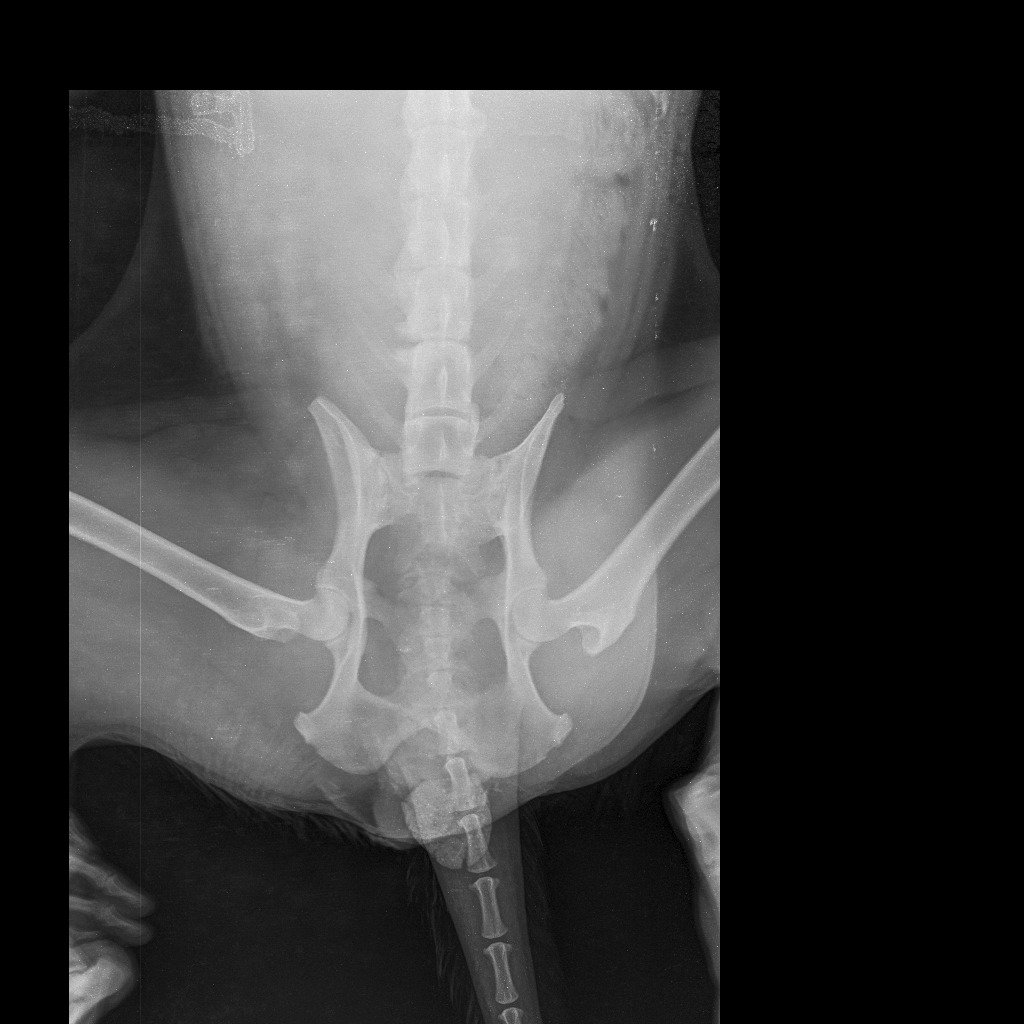

Gambina was found limping helplessly in a park, trembling in pain, after being struck by a car that didn’t stop to help. Her injuries are heartbreaking — she has a fractured rear left leg and tailbone. Because of the trauma, Gambina cannot control her bladder or bowels, and every moment without proper care worsens her condition.

Urgent surgery to repair her fractured leg and spine, and worse case scenario, possible amputation.